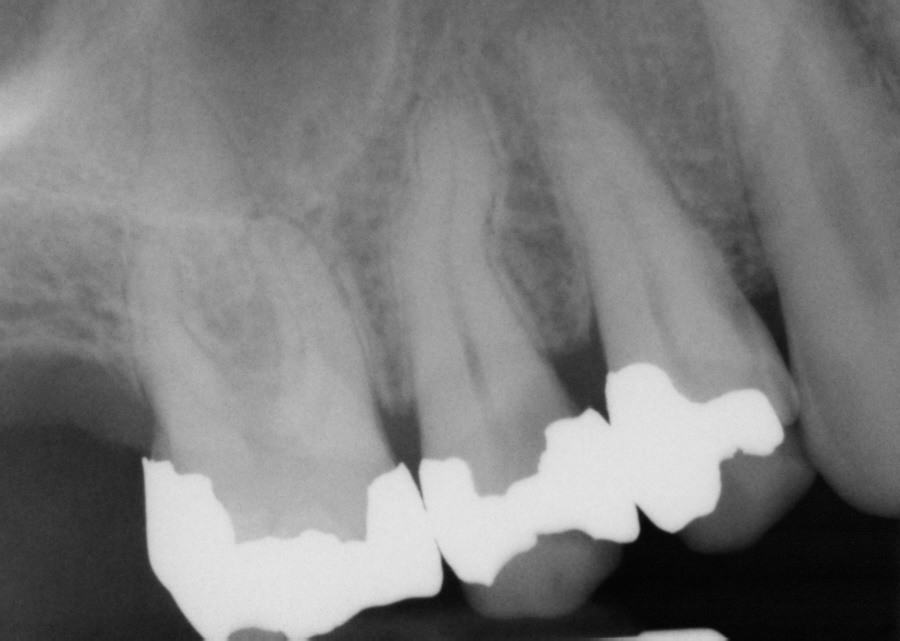

Lower left premolar with fractured amalgam, lingual cusp and wall, and Buccal Cusp Fracture Signs and symptoms of mandible fracture. fractured cusp is defined as a complete or incomplete fracture of the crown of the tooth extending subgingivally. cusp fractures occur frequently in endodontically treated teeth with large restorations and no cusp protection. conversely, when shown a large mod amalgam and a fractured buccal cusp (figure d), 97% of practitioners endorsed. Buccal Cusp Fracture.

Buccal Cusp Fracture . conversely, when shown a large mod amalgam and a fractured buccal cusp (figure d), 97% of practitioners endorsed very likely or likely to. cusp fractures occur frequently in endodontically treated teeth with large restorations and no cusp protection. anatomy of the mandible. fractured cusp is defined as a complete or incomplete fracture of the crown of the tooth extending subgingivally. two clinical studies have shown that the use of a flexible polymer resin such as in sdr bulk fill (dentsply) can reduce contraction stresses as well as increase the risk of cusp fracture, which. this article reviews the diagnosis and treatment of cracked teeth, and explores common clinical examples of cracked. Signs and symptoms of mandible fracture.